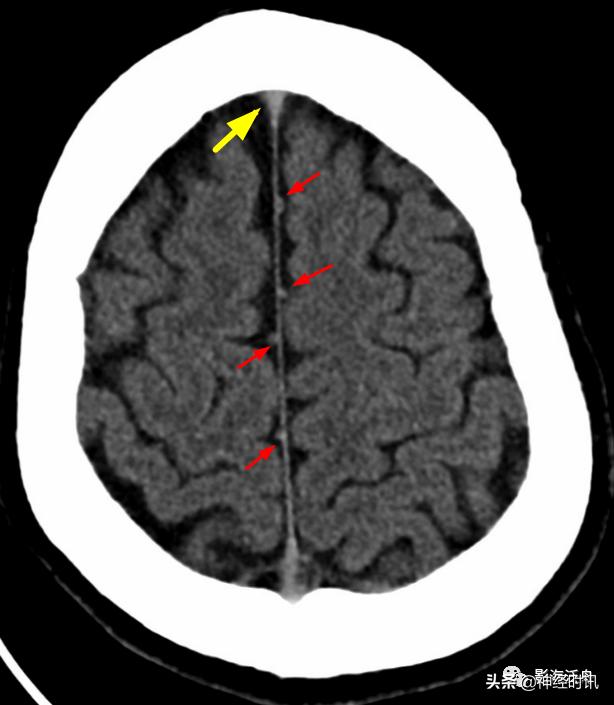

看完几个正常的,再来看一个异常的。2岁小孩,被电瓶车撞到后入院行头颅CT检查,大脑镰部多发短条状高密度影(红箭),注意和上面正常的大脑镰进行对比。

闭合性头颅外伤后,患者双侧大脑半球的多个脑回出现挫伤(红箭),损伤脑组织邻近的脑沟、脑裂少量积血,此即蛛血。由此可见蛛血的本质是脑表层(即脑灰质)挫伤后,血液沿破损的软脑膜流入到蛛网膜下腔,并在血清蛋白收缩作用下凝聚所致。也就是说,在凝血功能正常的情况下,程度较轻的外伤性蛛血引发大出血的概率极低。